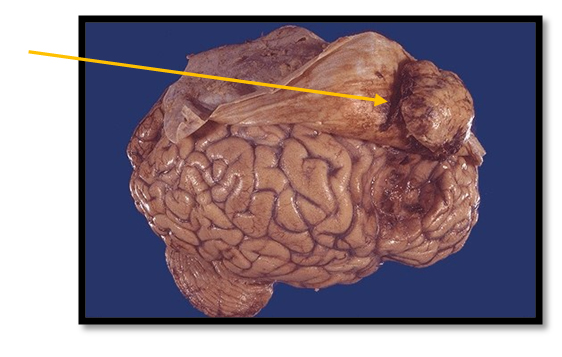

- Менингиому – наиболее распространена среди первичных доброкачественных опухолей. Между появлением опухоли и развитием первых симптомов может пройти достаточно длительный период длиной в несколько лет.

Менингиома |